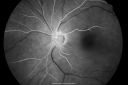

69-year-old man has a central retinal artery occlusion in his left eye with severe vision loss December 14th. I did an anterior chamber tap December 15th. His vision in that eye is still poor. I had him return for re-evaluation mostly because of the tap and also to make sure he did not start to develop rubeosis. His vision in the left eye is still poor. VISUAL ACUITY: Vision OS is light perception. IOP: 9. There is no rubeosis. There is a posterior chamber intraocular lens in good position. EXTENDED OPHTHALMOSCOPY: OS: Vertical C/D ratio is 0.8. The nerve is pale. The whitening of the retina looks to have subsided. IMPRESSION: 1. CENTRAL RETINAL ARTERY OCCLUSION – LEFT EYE

Central Retinal Artery Occlusion less than 24 hours - 69 year old man VA light perception996 views00000